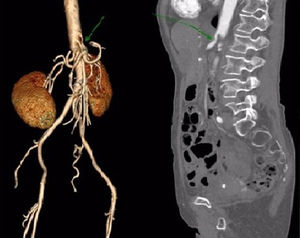

A 75-year-old female patient consulting for post-prandial epigastric pain associated with 5kg loss of weight in a year. An angio-tomography was performed, which showed proximal stenosis compatible with compression of the celiac trunk, suggestive of a median arcuate ligament syndrome (Fig. 1). An exploratory laparoscopy was performed with dissection of the vascular elements of the celiac trunk. The hepatic, splenic and left gastric arteries were identified and released until there onset (Fig. 2A and B). We recognized the celiac trunk of 2cm length. Release of the arcuate ligament and decompression of the celiac trunk was observed (Fig. 2C and D). The patient evolved favorably, with adequate oral intake and pain management.